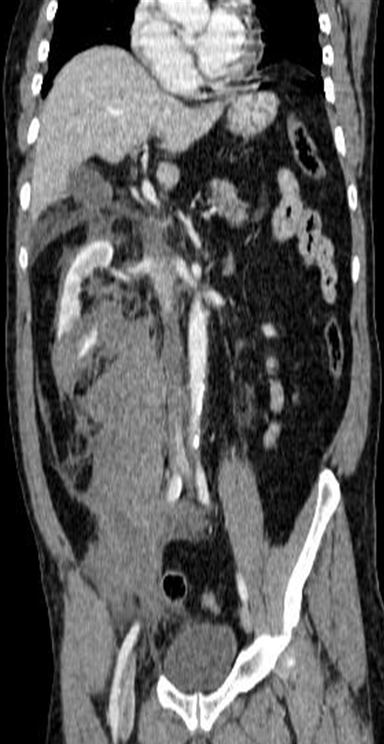

En este caso, se indica reconstrucción multiplanar del TC realizado, en la que se ve más claramente la laceración del polo renal inferior derecho y la expansión del hematoma perirrenal (riñón derecho).